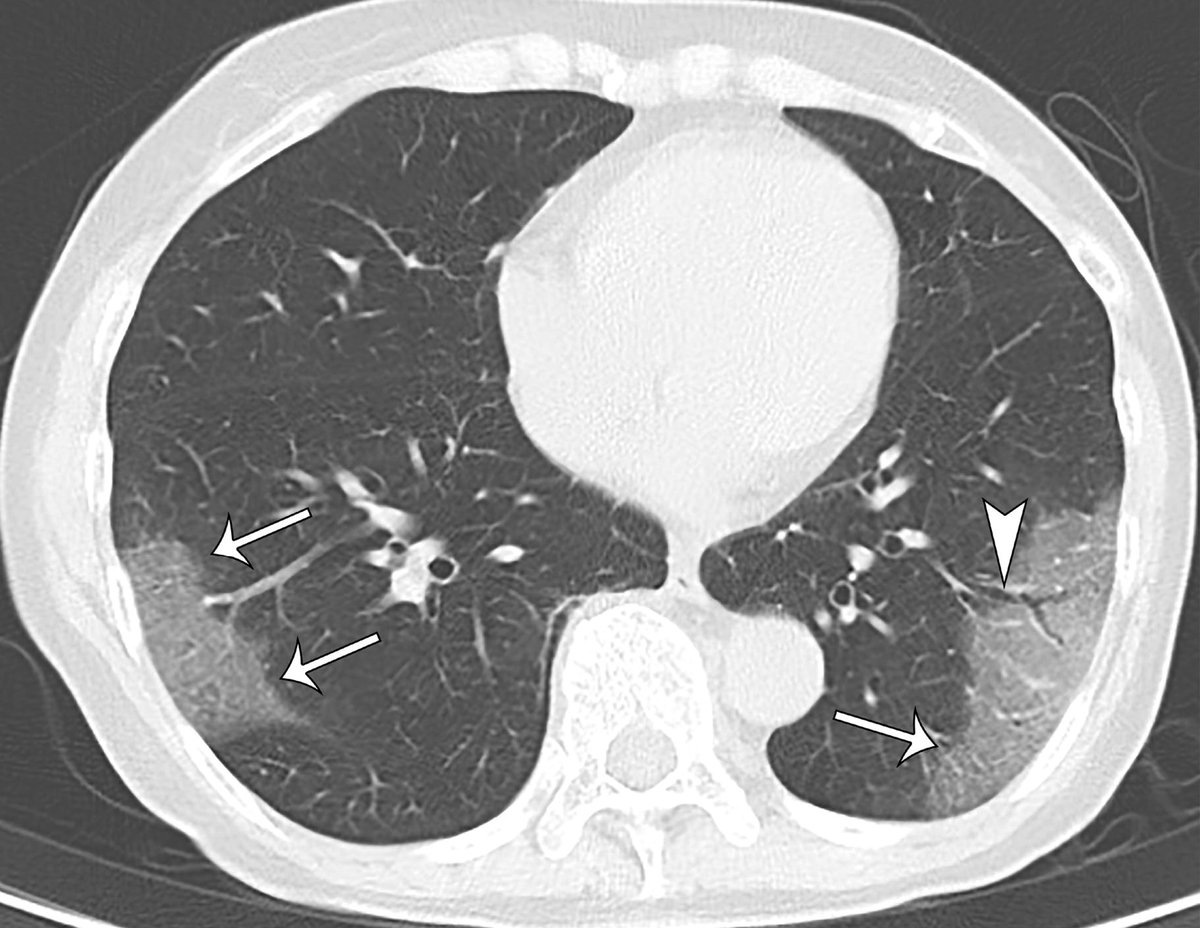

Как выглядят очаги матового стекла в легких

На снимках матовые пятна представлены темными областями низкой плотности, чередующимися со светлыми - уплотнений. Они покрыты мутным налетом. Это делает их похожими со своим названием. На участках матового стекла визуализируется усиленный рисунок бронхиальных стенок, сосудов легких. Заметны просветы бронхов, содержащие воздух. Паттерн матовых пятен хорошо различим на темном фоне. Заметить изменения сможет даже человек без специального образования.

Симптом "лоскутного одеяла" является одной из разновидностей матовых пятен. Для него характерно утолщение междольковых перегородок в областях повышенной плотности.

Другим специфическим проявлением является мозаичная плотность или мозаичная перфузия. При ней участки изменения чередуются в ткани легких.